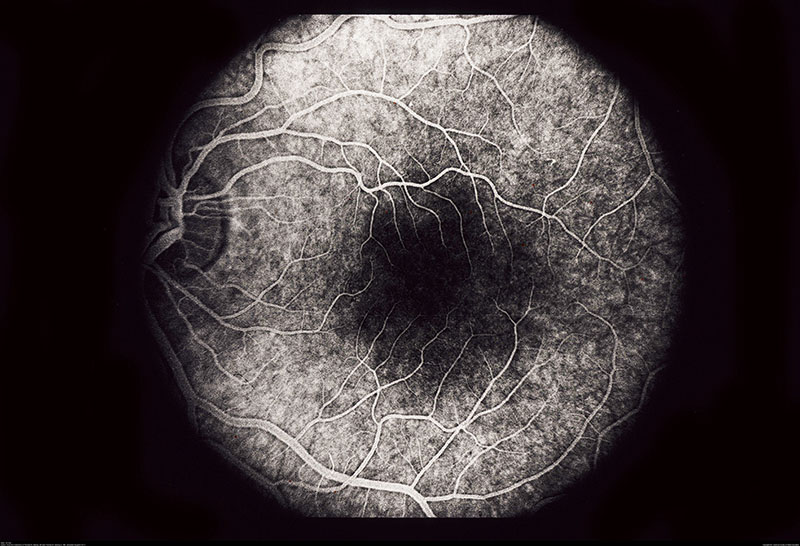

Friederich Dimmer developed the first fundus camera, was the first to incorporate fundus photography into an ophthalmic textbook, and published the first photographic retinal atlas in black-and-white. According to Dimmer’s original description, his fundus camera occupied an entire tabletop and only one such camera was ever produced.